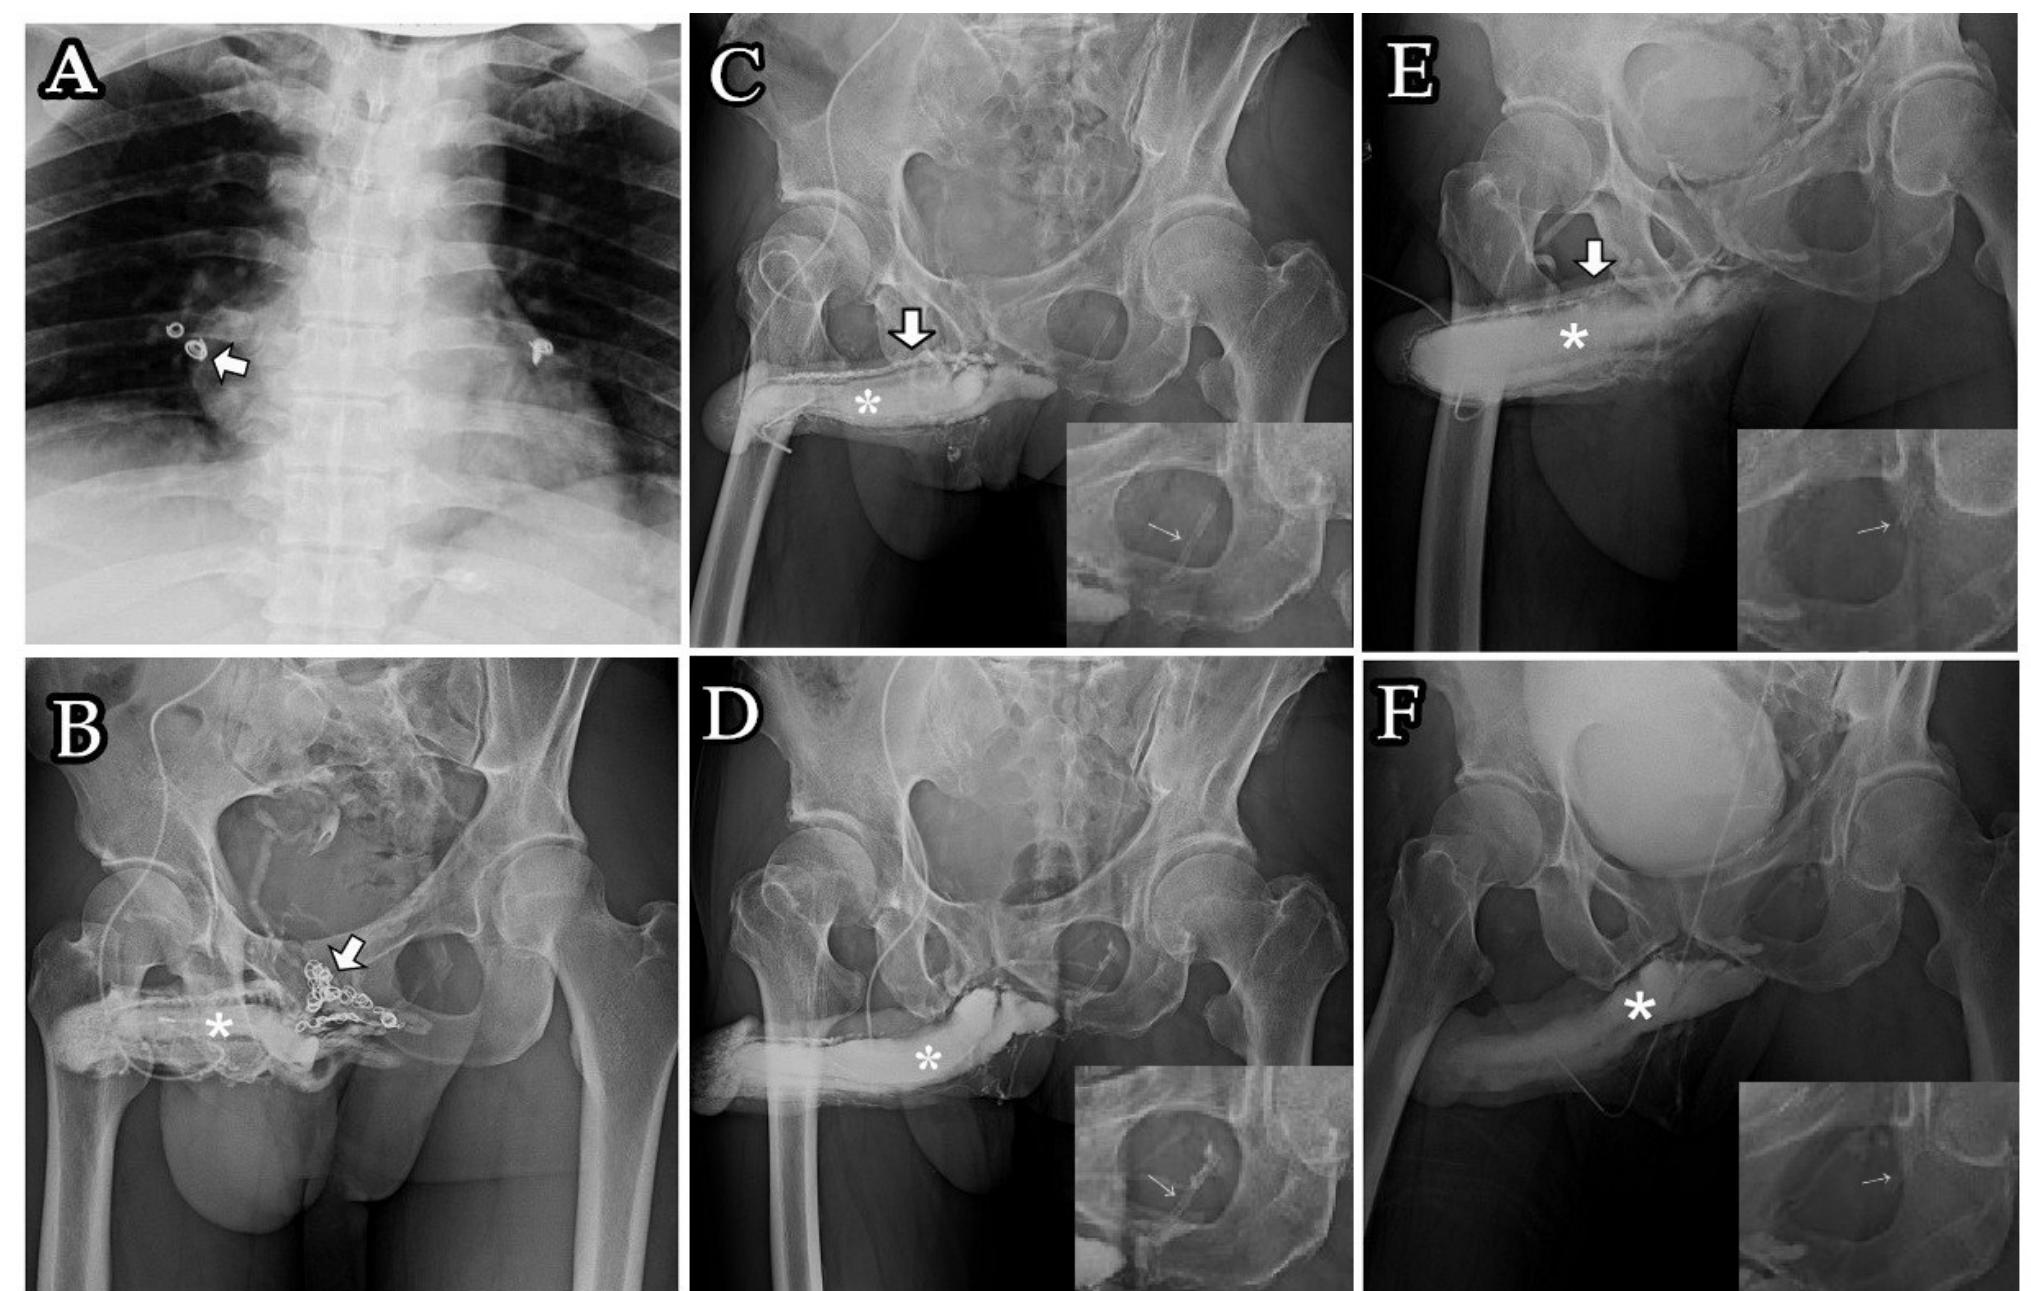

Penile Modification

Penile Modification 108 photos